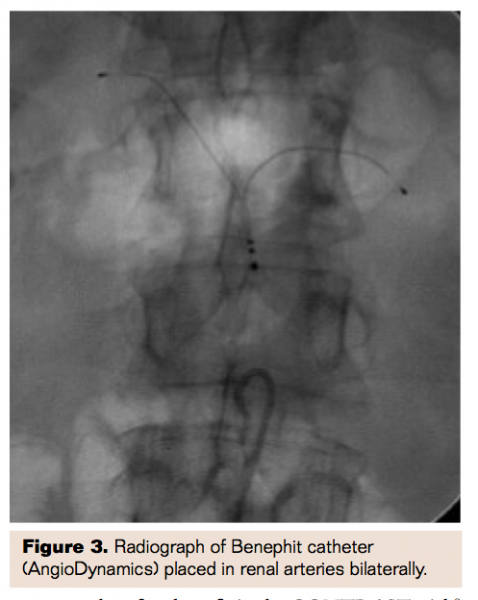

Given the pathophysiologic mechanisms of contrast nephropathy, there was interest in using intravenous fenoldopam, a dopamine-1 agonist and direct renal vasodilator, for prevention of contrast nephropathy. This approach quickly gained popularity but ultimately was proven to be of no benefit in the CONTRAST trial.8 The likely reason for failure was elucidated in work done by Tierstein et al9 which evaluated the effect of intravenous vs intrarenally (IR) delivered fenoldopam. Tierstein demonstrated that there was no increase in renal blood flow or glomerular filtration rate associated with the doses of intravenous fenoldopam utilized in CONTRAST and higher doses were not possible due to limitations of systemic hypotension. Conversely, IR fenoldopam delivered using a specialized bifurcated “Benephit” catheter (Figures 2, 3; AngioDynamics) significantly increased renal blood flow and GFR by 25% and allowed the delivery of much higher doses of fenoldopam, typically 0.4 mcg/kg/min compared to 0.05 mcg/kg/min to 0.1 mcg/kg/min delivered intravenously. The prophylactic administration of IR fenoldopam for prevention of CIN became known as “targeted renal therapy” (TRT).

Multicenter, nonrandomized data was collected in the Be-RITE Registry.10 A total of 501 patients were treated between May 2004 and August 2007 at 19 centers and 285 of those undergoing percutaneous procedures were evaluable for CIN incidence at 48 hours. Patients received 145±78 mL of contrast. Baseline mean Cr was 2.01±0.58 mg/dL and 96% of patients had a baseline Cr>1.5 or CrCl<60 mL/min with mean baseline CrCl of 37±12 mL/min.

Placing the Benephit catheter was fairly simple with 95% success rate and average time to bilateral renal artery cannulation of 2.0±1.6 minutes. Infusion times varied considerably at 199±212 minutes. Mean creatinine levels were unchanged at 48 hours (2.00±0.73, P=.56). The predicted incidence of contrast nephropathy in this high-risk group using the Mehran model was 28.0% whereas the observed incidence of CIN was only 8.1%, a relative risk reduction of 71% (P<.0001).